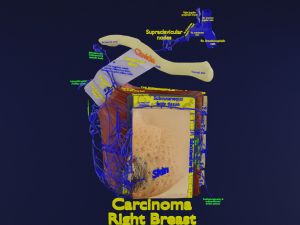

This is a 1:1 scaled model of right breast cut opened in sagittal plane to reveal its internal antomy and histology (schematic). The deeper parts and fascial layers are also depicted to give a very detailed approach to the model. The full layers starting from skin, nipple areola, till intercodtal muscles and ribs are also depicted.

breast mammary gland female chest wall anatomy human medical science reproductive genitalia muscle fascia milk nipple areola subcutaneous fatДо даного товару немає коментарів.